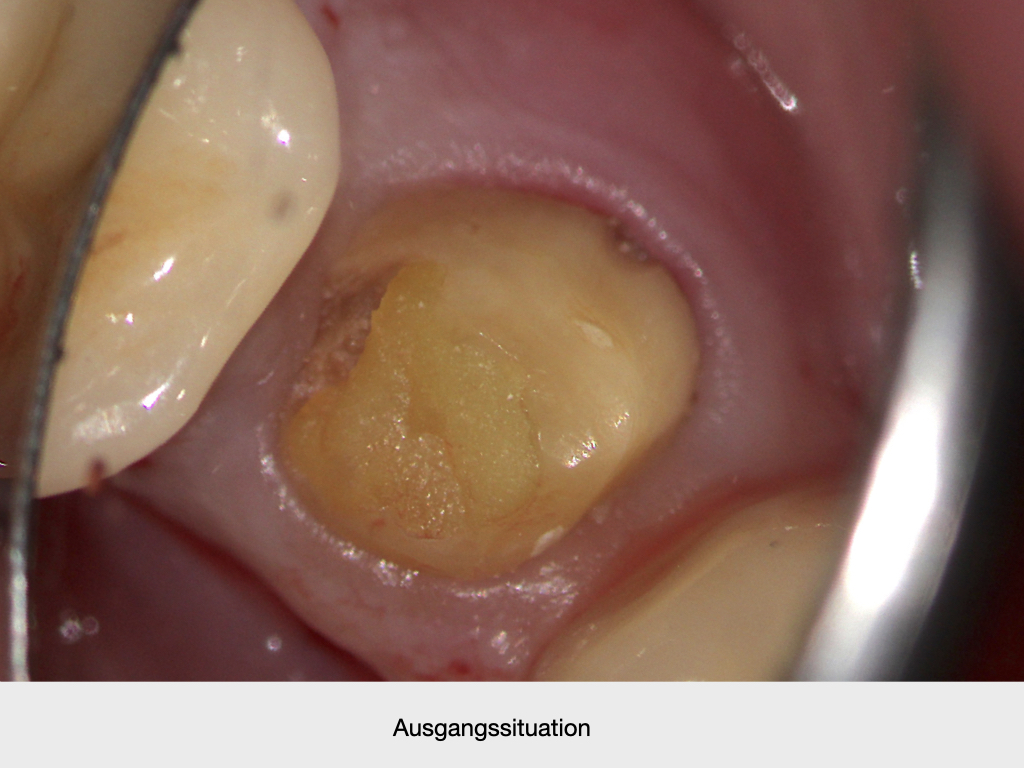

Lateraler Kanal